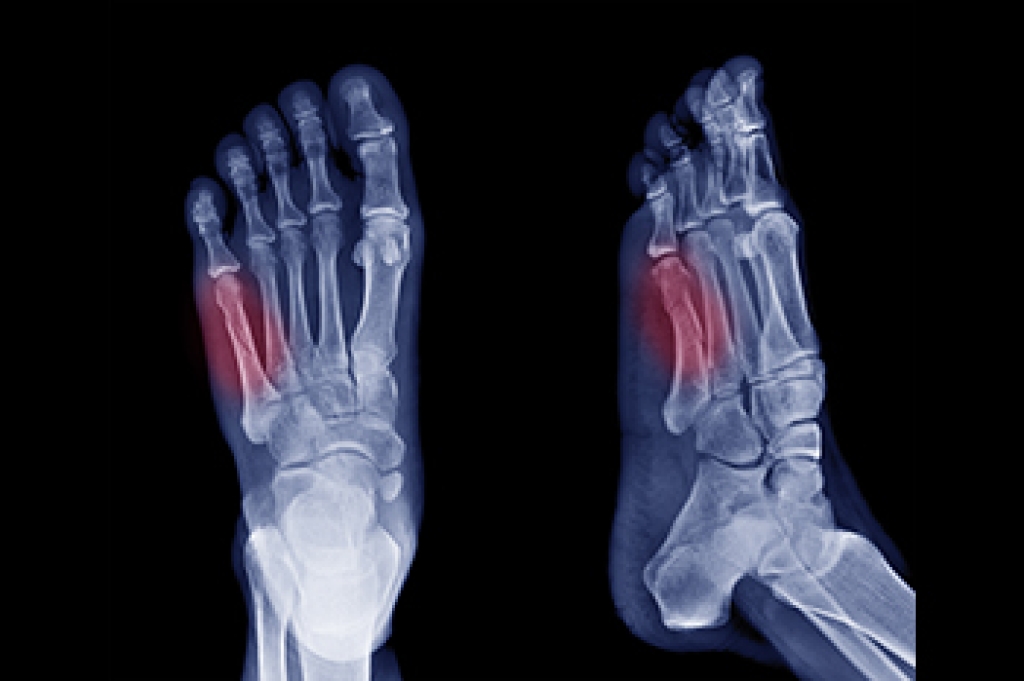

As we age, our feet undergo various changes, often leading to discomfort and mobility issues. Treatment for common foot ailments among seniors varies, depending on the condition. Bunions may require shoe modifications, custom orthotics, medication, or surgery from a podiatrist. Hammertoe deformities may necessitate changes in footwear or in some cases surgery. Toenail problems, including ingrown nails and infections, require professional attention to prevent complications, with podiatrists offering specialized care and treatment options. Seniors with diabetes must prioritize foot health and regular podiatric evaluations to prevent serious complications, such as foot ulcers or gangrene. Plantar fasciitis treatment ranges from conservative measures, such as exercises, to surgery for effective relief. Arch problems, whether flat feet or high arches, generally necessitate a non-surgical approach along with expert guidance to manage discomfort and prevent further complications. For help with any of the many foot conditions common among seniors, it is suggested that you schedule an appointment with a podiatrist for a thorough foot exam, diagnosis, and treatment options.

- Foot sores – amongst the older population can be serious before they are discovered. Some of the problematic conditions they may face are: